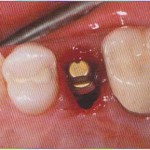

Пациентка согласилась на план лечения, включавший в себя поднятие д...